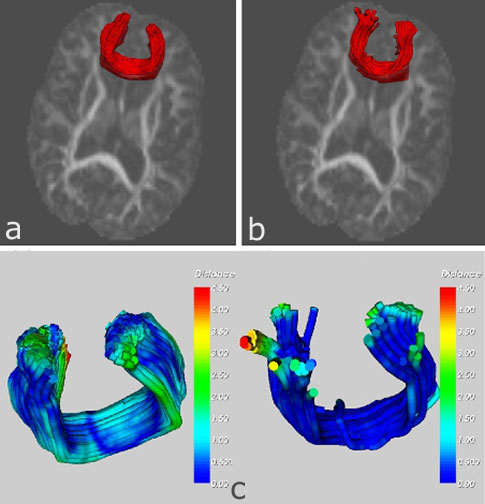

Group analysis of DTI fiber tract statistics with application to neurodevelopment. The genu tract (a) mapped from atlas is compared with (b) the tract produced by tractography in the individual. Comparison of pointwise distances between the two fiber tracts reveals a maximum difference of 4.5 mm between the two tracts. The average distance in the main body of the tract is less than 1.5 mm. Read more...